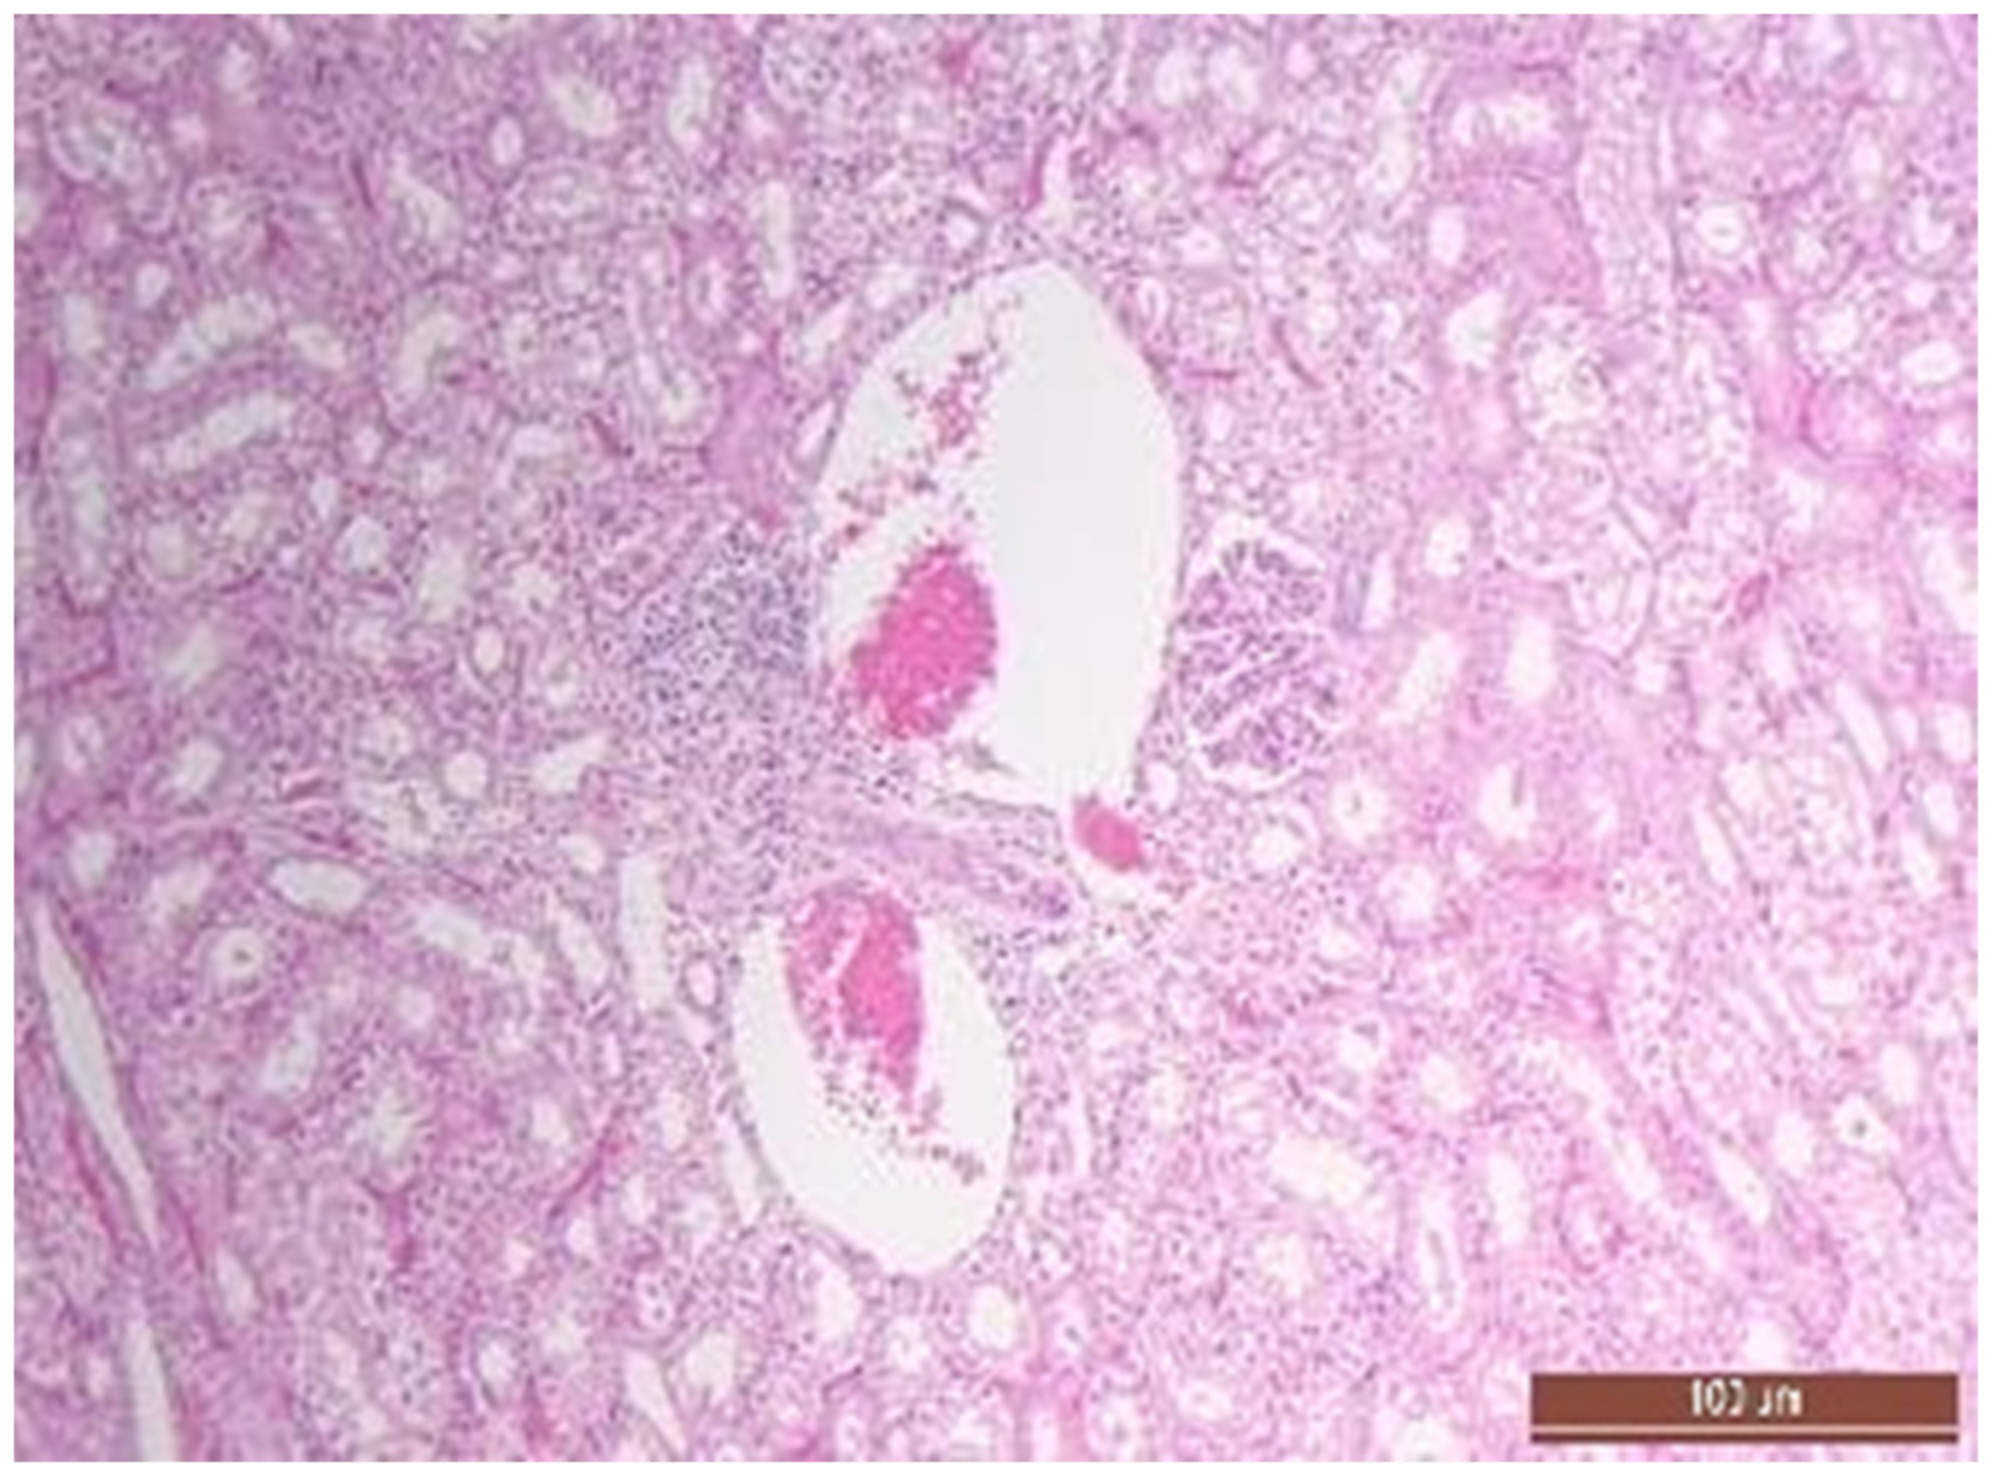

3.2. Pathology of the Liver

3.4. Pathology of Kidneys